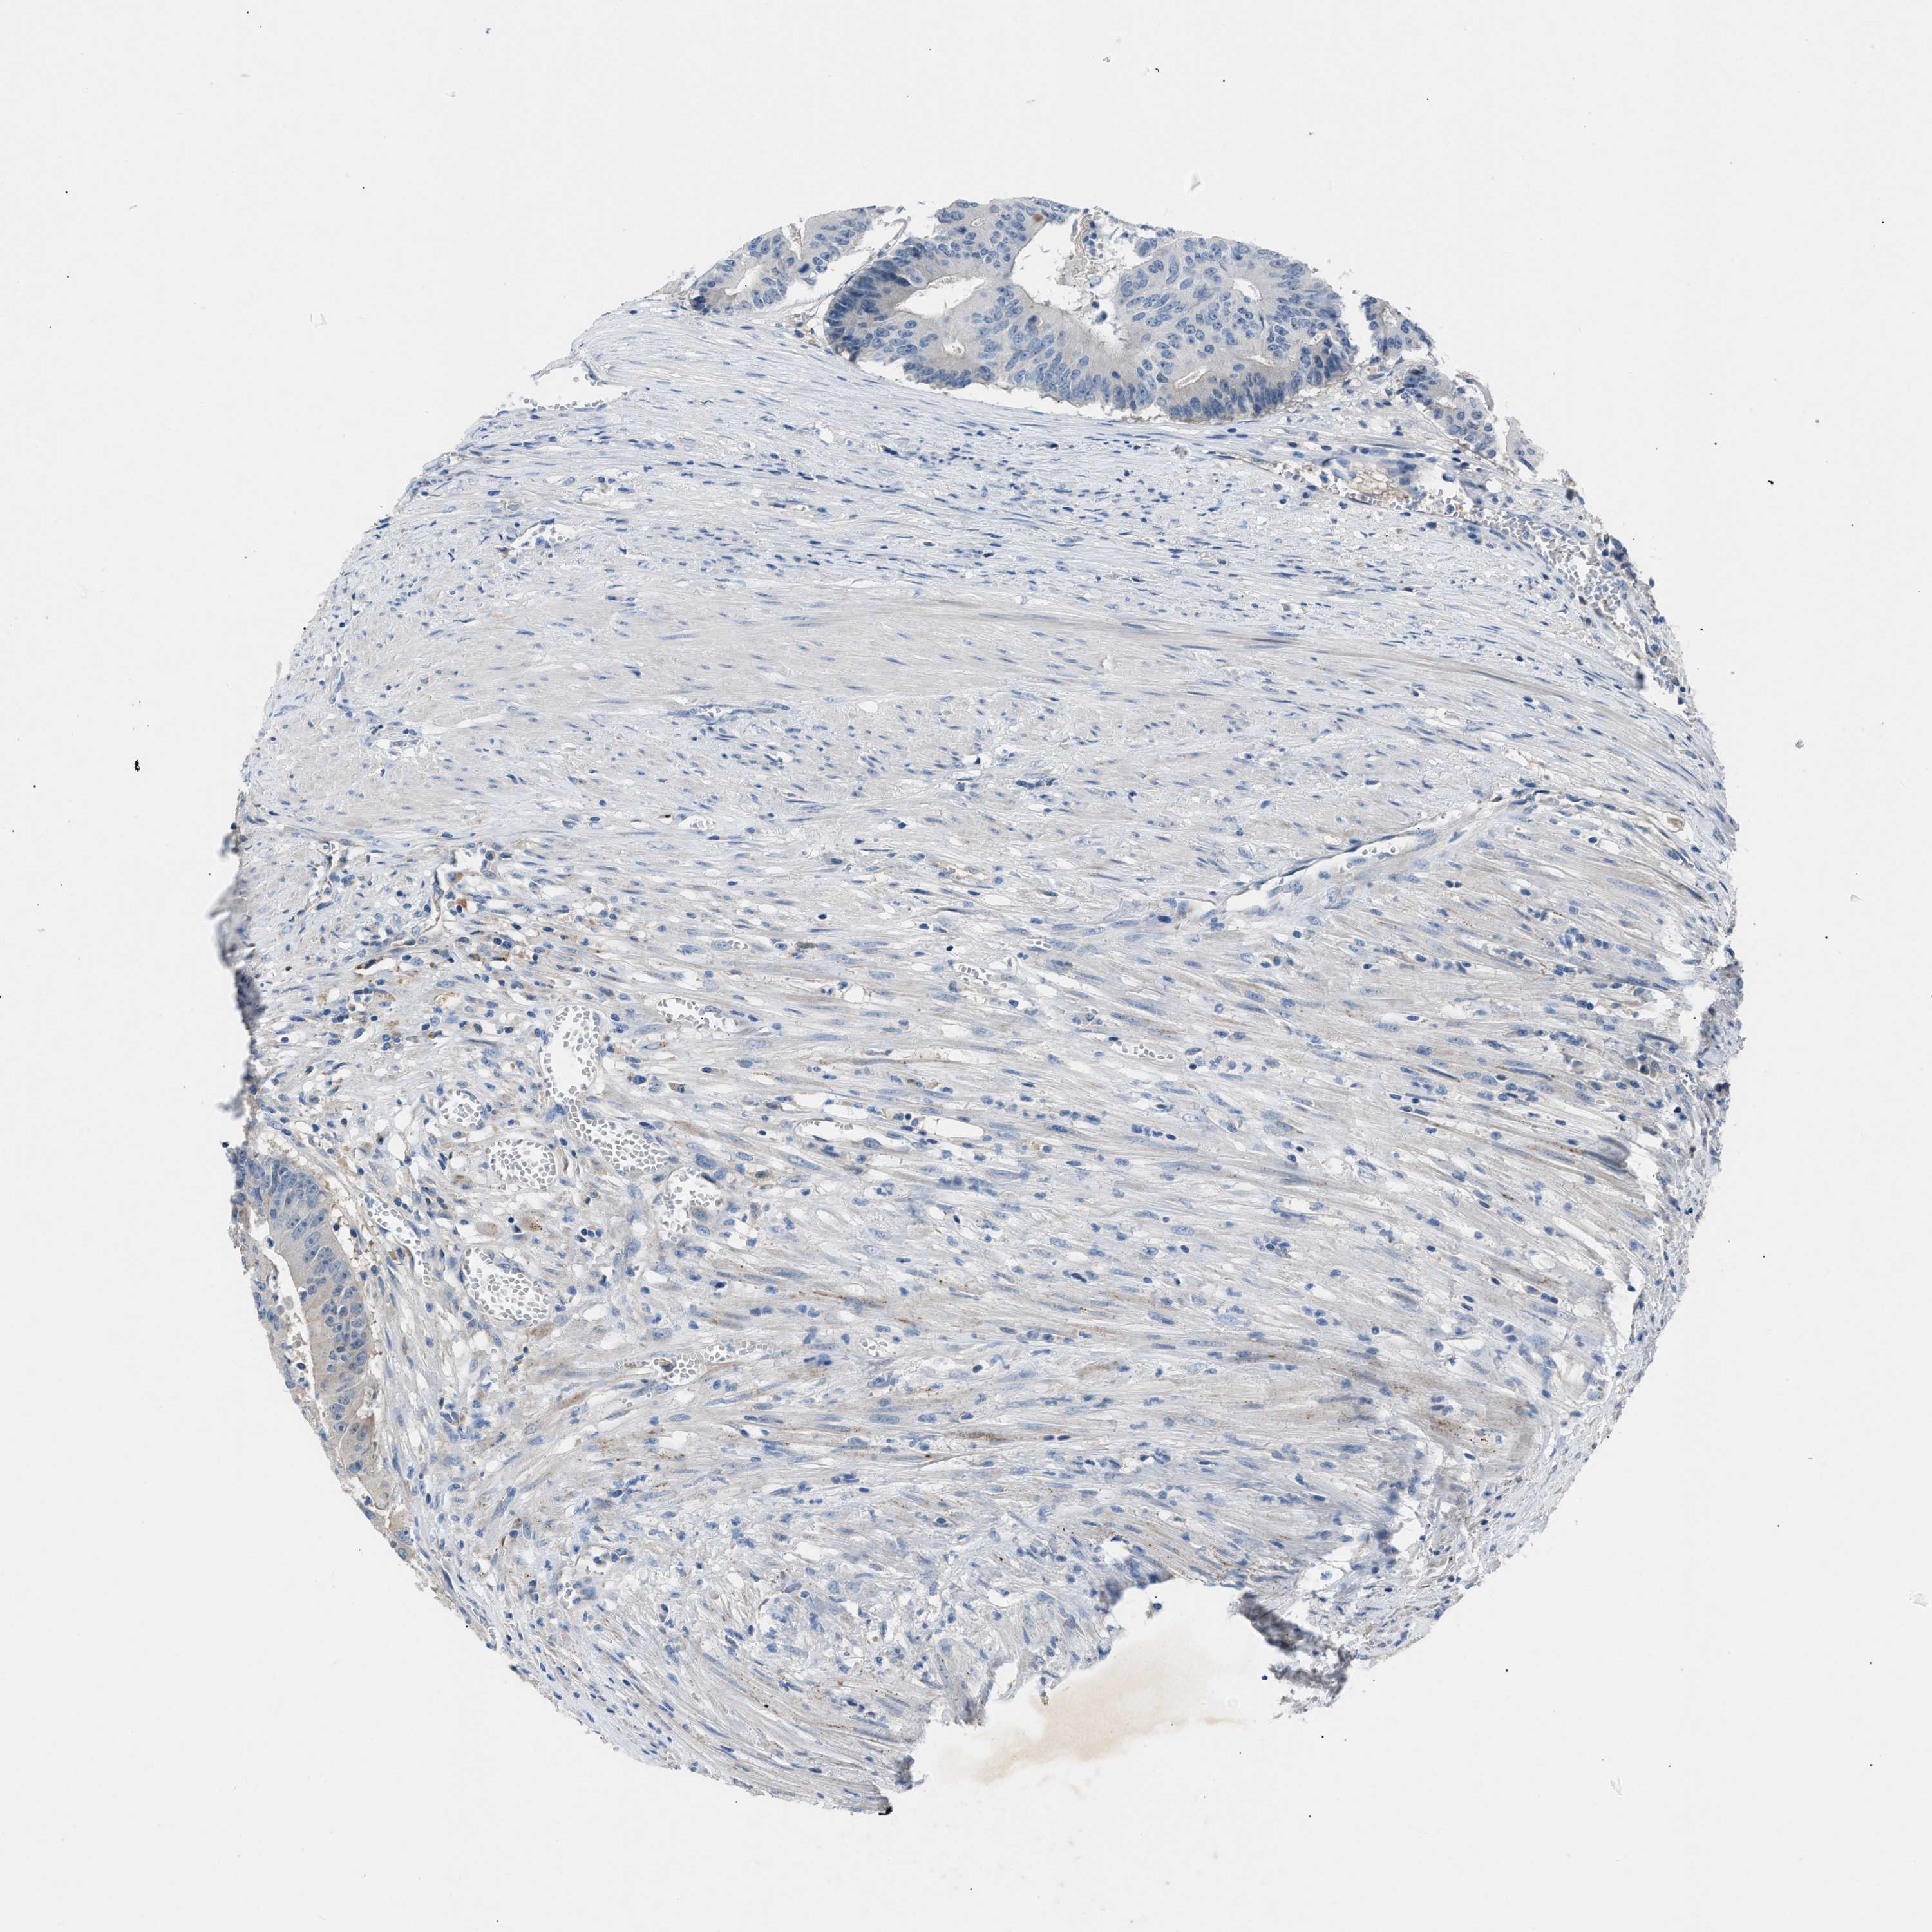

CANCER COLORECTAL CANCER Show tissue menu

Colorectal cancer

Human cancer

Colon adenocarcinoma